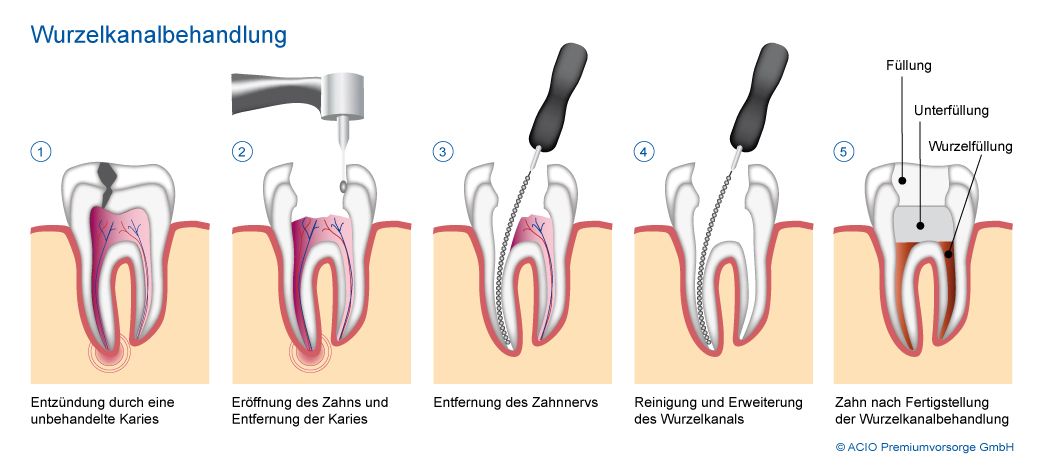

Με την απονεύρωση ο ενδοδοντολόγος αφαιρεί το νεκρό ή μολυσμένο πολφό, όπως και τα νεύρα του δοντιού. Αφού επεξεργαστεί και καθαρίσει πλήρως το δόντι σε 2 ή 3 συνεδρίες,ανάλογα με το βαθμό δυσκολίας του δοντιού, στη συνέχεια εμφράσσονται οι ριζικοί σωλήνες με ένα ειδικό υλικό που λέγεται γουταπέρκα. Σκοπός της έμφραξης των ριζικών σωλήνων είναι η αποφυγή επαναμόλυνσης του πολφού. Στη συνέχεια ακολουθεί η αποκατάσταση του δοντιού με σφράγισμα ή στεφάνη ανάλογα με το έκταση της οδοντικής βλάβης.